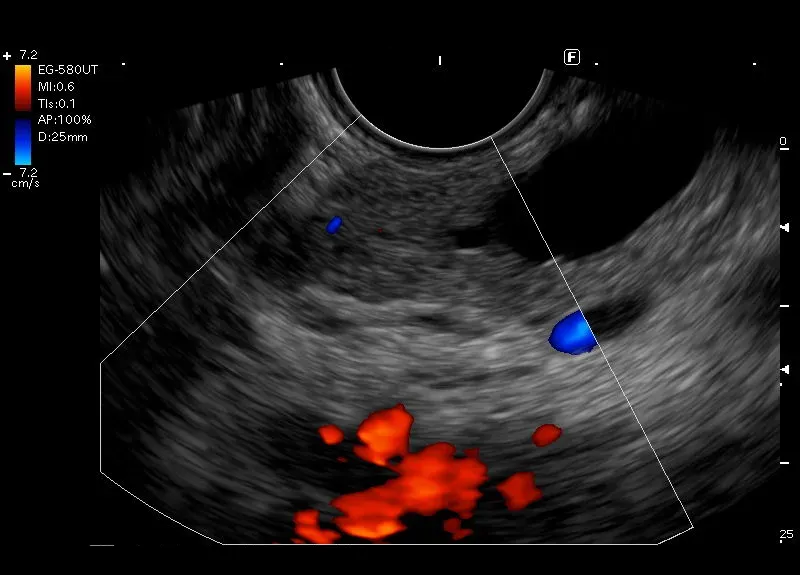

Widoczne w trzonie trzustki

torbielowate poszerzenie przewodu Wirsunga - obraz może odpowiadać MD-IPMN

( Main-Duct Intraductal Papillary Mucinous Neoplasms).